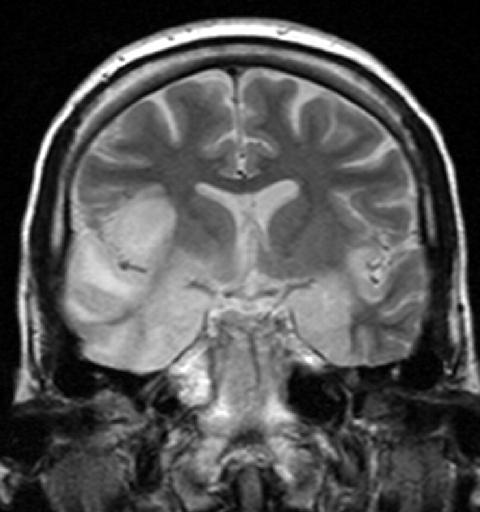

Диагностика герпетического поражения головного мозга